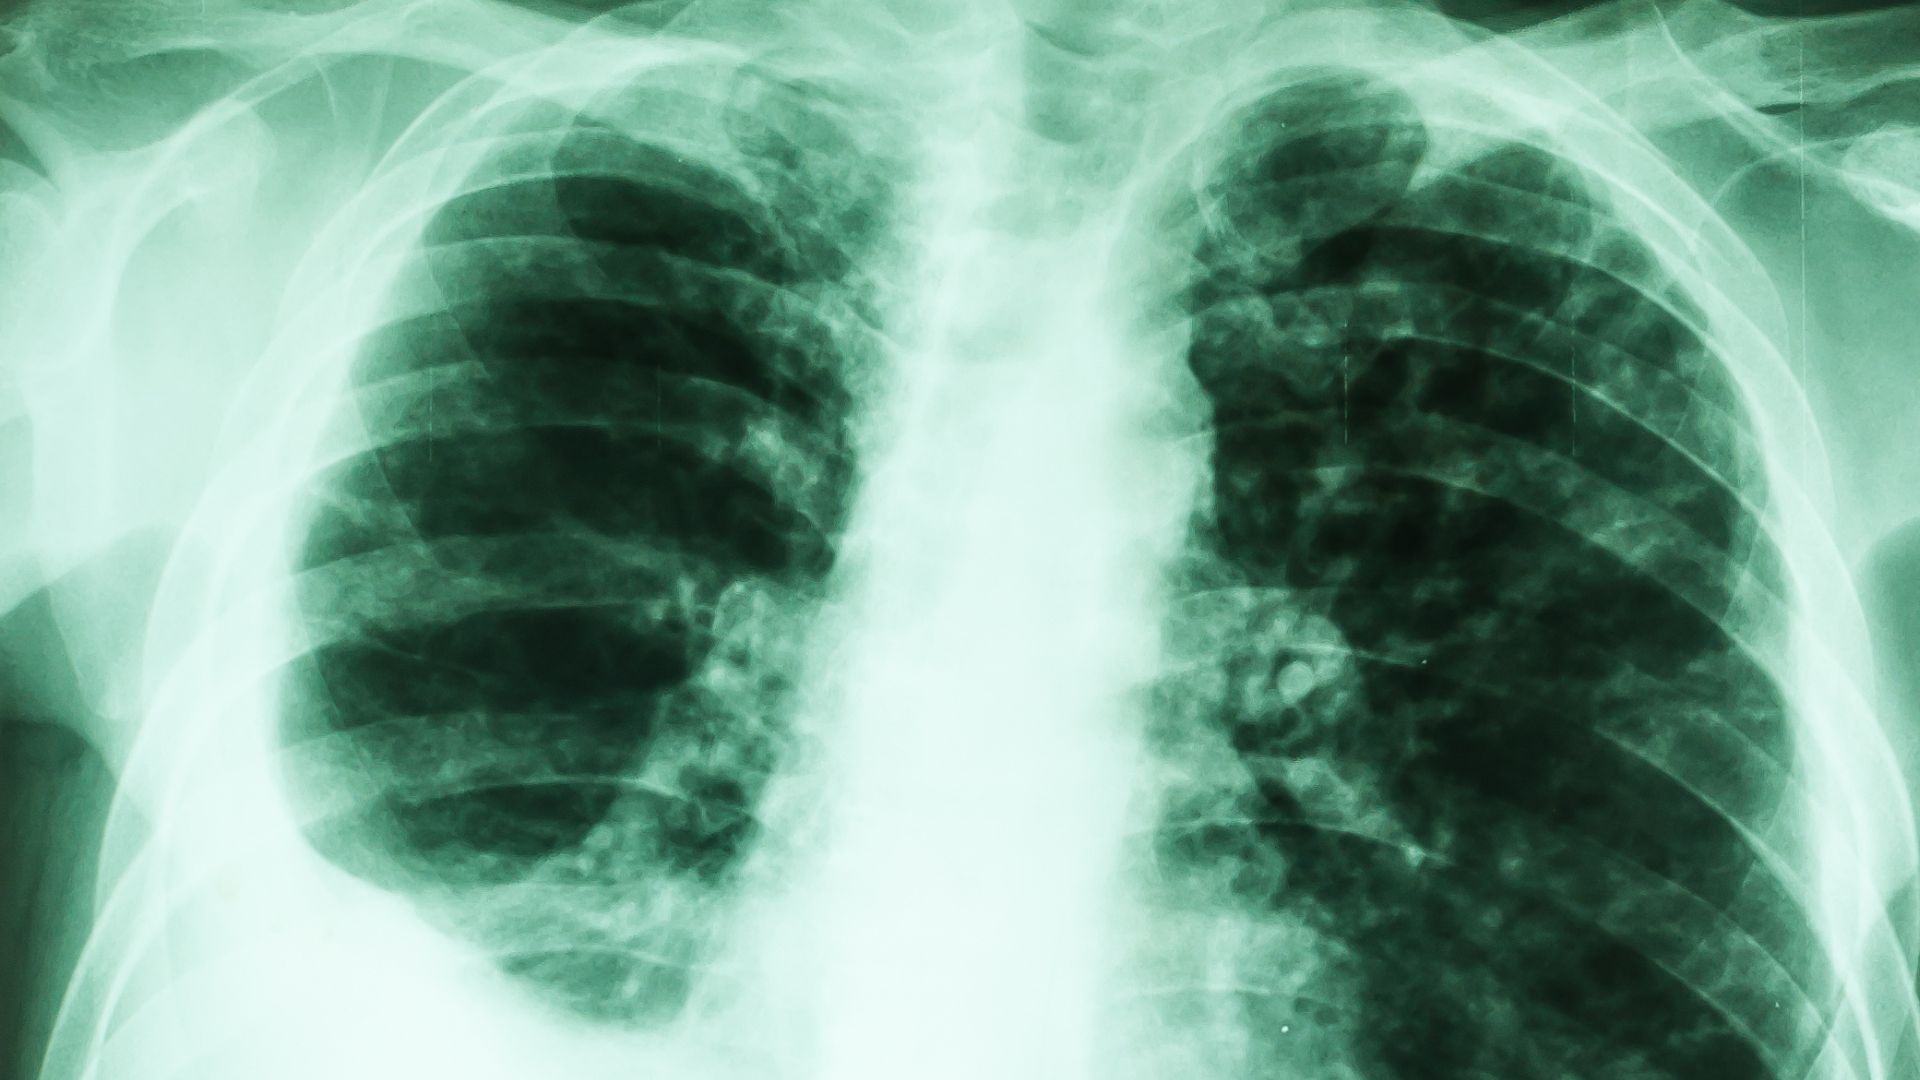

Nội soi màng phổi (pleuroscopy hoặc medical thoracoscopy) là thủ thuật sử dụng ống nội soi mềm hoặc cứng, có gắn camera và nguồn sáng, đưa qua thành ngực vào khoang màng phổi. Nhờ đó, bác sĩ có thể quan sát trực tiếp bề mặt màng phổi, phổi và các tổn thương bất thường mà các phương pháp chẩn đoán hình ảnh khó đánh giá chính xác.

- Theo dõi sau thủ thuật và chụp X-quang kiểm tra.